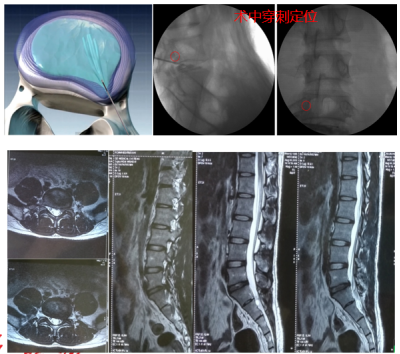

2.以上疗效不佳,可进行椎间孔镜微创治疗;

3.椎体压缩性骨折:经皮椎体成形术(球囊骨水泥)、经皮钉棒内固定治疗压缩性骨折。